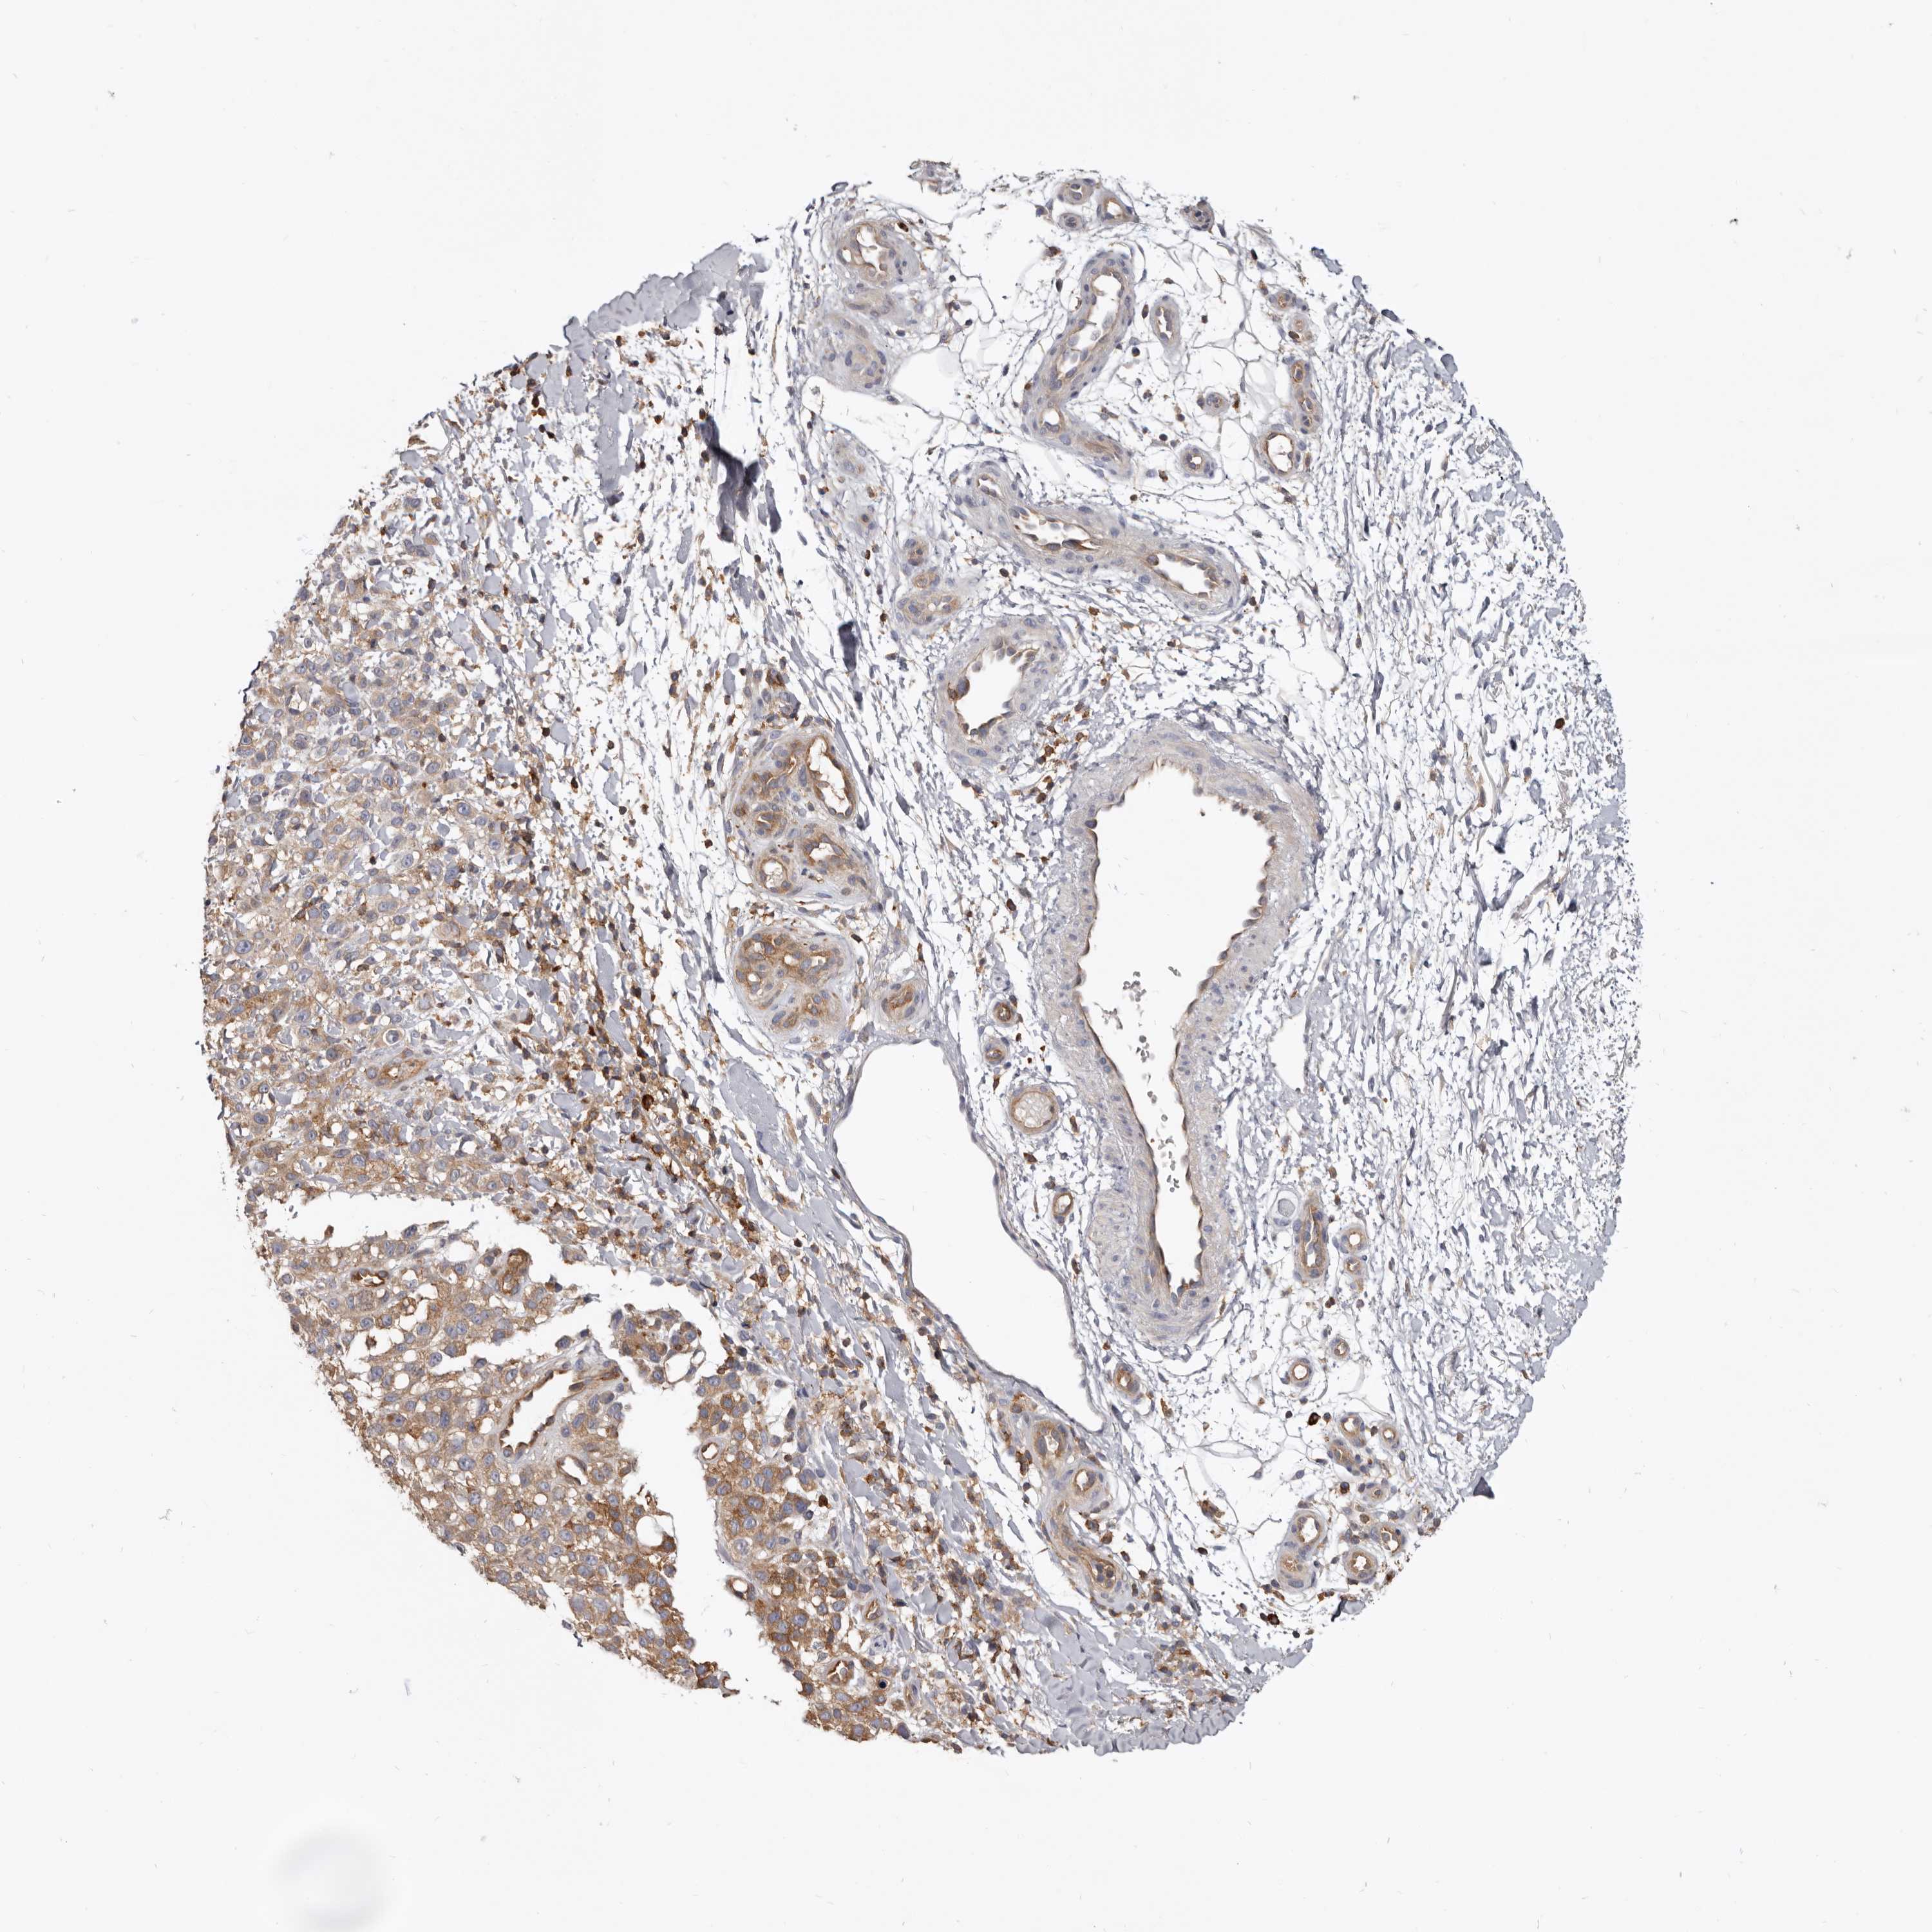

MELANOMA - Protein expressioni

A mouse-over function shows sample information and annotation data. Click on an image to view it in a full screen mode. Samples can be filtered based on level of antibody staining by selecting one or several of the following categories: high, medium, low and not detected. The assay and annotation is described here.

Note that samples used for immunohistochemistry by the Human Protein Atlas do not correspond to samples in the TCGA dataset.

Antibody stainingi

Antibody staining in the annotated cell types in the current human tissue is reported as not detected, low, medium, or high, based on conventional immunohistochemistry profiling in selected tissues. This score is based on the combination of the staining intensity and fraction of stained cells.

Each image is clickable and will lead to virtual microscopy that enables deeper exploration of all samples and also displays staining intensity scores, fraction scores and subcellular localization as well as patient and tissue information for each sample.

Antibody HPA027956

Antibody CAB004350

Staining

High

Medium

Low

Not detected

Intensity

Strong

Moderate

Weak

Negative

Quantity

>75%

75%-25%

<25%

None

Location

Nuclear

Cytoplasmic/membranous

Cytoplasmic/membranous,nuclear

Malignant melanoma, NOS

Malignant melanoma, Metastatic site